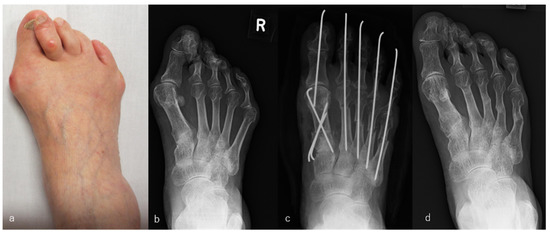

Figure 2.

Rheumatoid arthritis (RA) in a 53-year-old woman. Metatarsophalangeal joint-preserving surgery involving the modified Mann method was performed for the big toe, and resection arthroplasty was performed for lesser toes. RA had been present for 29 years. The patient received methotrexate (4 mg/week), tacrolimus (2 mg/day), and sulfasalazine (1000 mg/day). Radiographic views of her left foot before surgery (a), immediately after surgery (b), and 8 years after surgery, which was the latest follow-up (c). Scores on the Japanese Society for Surgery of the Foot RA foot and ankle scale improved from 50 points before surgery to 84 points at the 8-year follow-up. The mean hallux valgus angle improved from 32° before surgery to 9° immediately after surgery and was 16° at the 8-year follow-up. The patient was satisfied with the clinical results at the 8-year follow-up, although the correction of the hallux valgus angle had decreased slightly and the metatarsal bone had shortened compared with the values immediately after surgery.